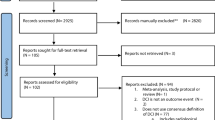

A systematic review of the literature was performed to identify peer-reviewed literature reporting association of radiological evidence of blood-brain barrier integrity with clinical or radiological outcomes following aSAH in humans. The approach for reporting was modelled on the PRISMA guidelines (Fig. 2). We conducted a literature search using the PubMed/MEDLINE database using the search terms “(subarachnoid haemorrhage OR SAH) AND (blood-brain barrier OR BBB) AND (magnetic resonance imaging OR MRI OR computed tomography OR CT OR imaging)”. Abstracts were screened for investigations of association of radiological evidence of BBB permeability and clinical or radiological outcomes pertaining to DCI. Eight studies were included in the qualitative synthesis of the literature, presented as a narrative review describing the utility of permeability imaging in predicting DCI or poor outcomes in humans with aSAH [20, 34,35,36, 38, 43, 48, 62].